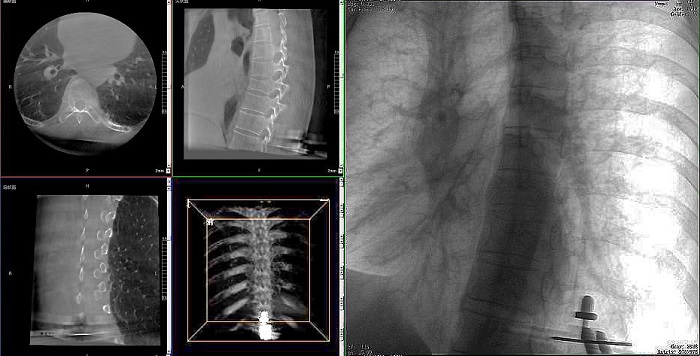

患者:71歲,男性,胸8椎體壓縮性骨折

術式:機器人輔助經皮釘棒系統復位內固定手術

①機器人輔助胸椎手術操作難點之圖像采集

胸椎緊鄰肺部,患者的呼吸運動會造成椎節的相對移動,獲取清晰、穩定的影像較為困難。高質量的影像是精準導航的重要前提,胸椎手術中,如果呼吸造成的移動無法得到有效控制,則會降低導航的精度,增加手術風險。人體深吸氣胸圍與深呼氣胸圍的差值約為6~8厘米。

高清三維成像:普愛醫療精研三維成像技術13年,自研的三維C形臂可為手術提供清晰、穩定的三維圖像,為醫生精準開展胸椎手術提供影像保障。

快速掃描:麻醉師通過適當的呼吸控制,配合三維C形臂的快速掃描模式,可以在短時間內完成圖像采集,減少因呼吸運動造成的圖像干擾。